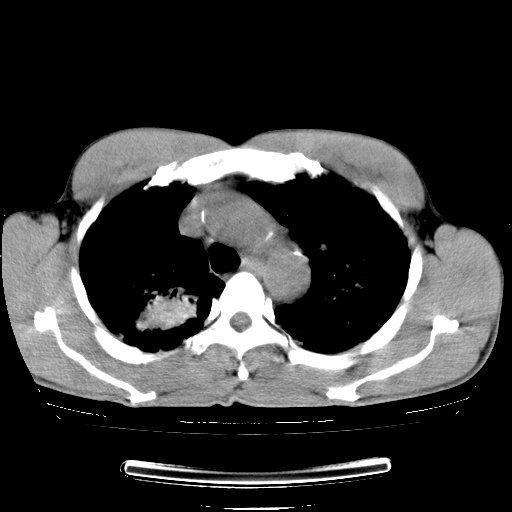

以下是引用yangyudong333在2008-4-29 5:38:00的发言:[br]比较典型的矽肺结节.支持[br]诊断依据:[br] 1.x线表现:[br] ①典型矽肺为多发直径 1~3mm 小结节,即矽结节,由胶原纤维和硅尘构成,可融合成团块,好发于上肺。[br] ②团块周围常有肺大泡。[br] ③胸内淋巴结增大、钙化。如肺门淋巴结呈蛋壳样钙化有助于与其他尘肺区别。[br] ④胸膜常广泛粘连、增厚。[br] 2.ct表现[br] ①两肺散在大小较为一致的小结节影,其密度较高,边界清楚。[br] ②小结节可融合为较大团块影,直径约 1cm ,甚至可达 10cm以上,易发生在上叶。[br] ③小结节周围常并有小叶中心气肿或弥漫性肺气肿。

以下是引用liuyue在2008-4-28 22:30:00的发言:[br]比较典型的矽肺结节.[br]请结合临床及化验除外矽肺合并肺结核之可能.